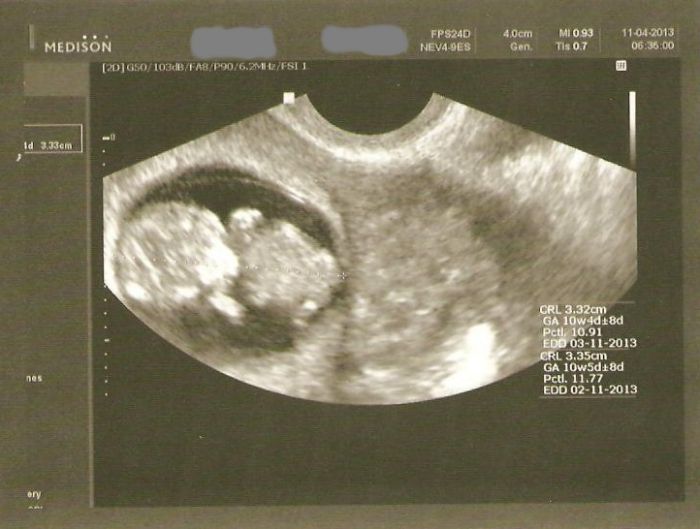

ahoj holky .. poslušně hlásím, že je vše v naprostém pořádku a mimiško pěkně roste. Už jsem viděla mimiško, jak má být ... řeknu vám... nádhera, aj slzička ukápla

dnes mám zase jiný týden... podle UTZ jsem dnes 10+4 to jsou mi změny... takže to vypadá, že se vracím k původnímu termínu dle PMS 30.10. ještě, že jsem založila říjen/listopad

. přikládám novou fotečku a těším se, až si přečtu vaše zprávy a uvidím fotečky... držte se